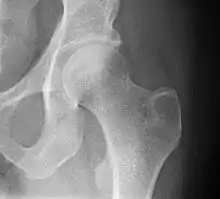

X-ray showing a suspected compressive subcapital fracture as a radiodense line

CT scan shows the same, atypical for a fracture since the cortex is coherent

T1-weighted, turbo spin echo, MRI confirms a fracture, as the surrounding bone marrow has low signal from edema.